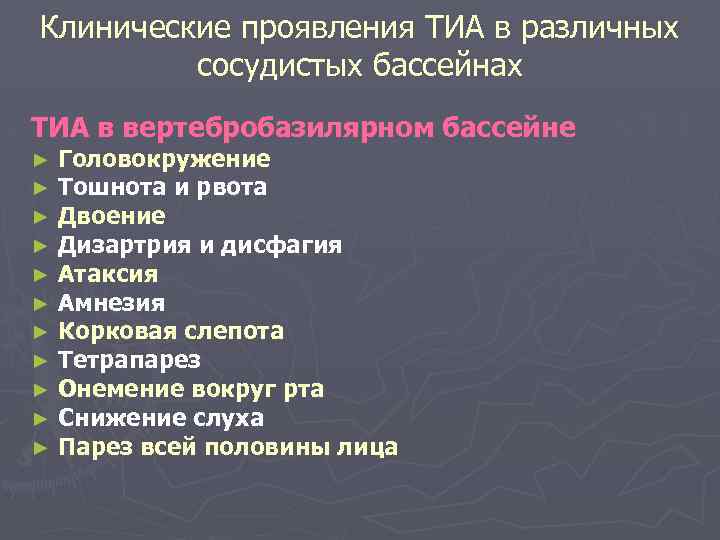

Клинические проявления ТИА в различных сосудистых бассейнах ТИА в вертебробазилярном бассейне ► ► ► Головокружение Тошнота и рвота Двоение Дизартрия и дисфагия Атаксия Амнезия Корковая слепота Тетрапарез Онемение вокруг рта Снижение слуха Парез всей половины лица